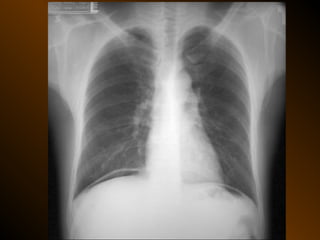

KHÍ TỰ DO

TRONG KHOANG PHÚC MẠC

NGUYÊN NHÂN

thủng tạng rỗng

nguồn gốc xuyên phúc mạc

nguồn gốc trong phúc mạc

10 – 15% thủng tạng rỗng → không thấy hơi tự do ổ bụng

KHÍ TỰ DO TRONGKHOANG PHÚC MẠC NGUYÊN NHÂN thủng tạng rỗng nguồn gốc xuyên phúc mạc nguồn gốc trong phúc mạc 10 – 15% thủng tạng rỗng → không thấy hơi tự do ổ bụng